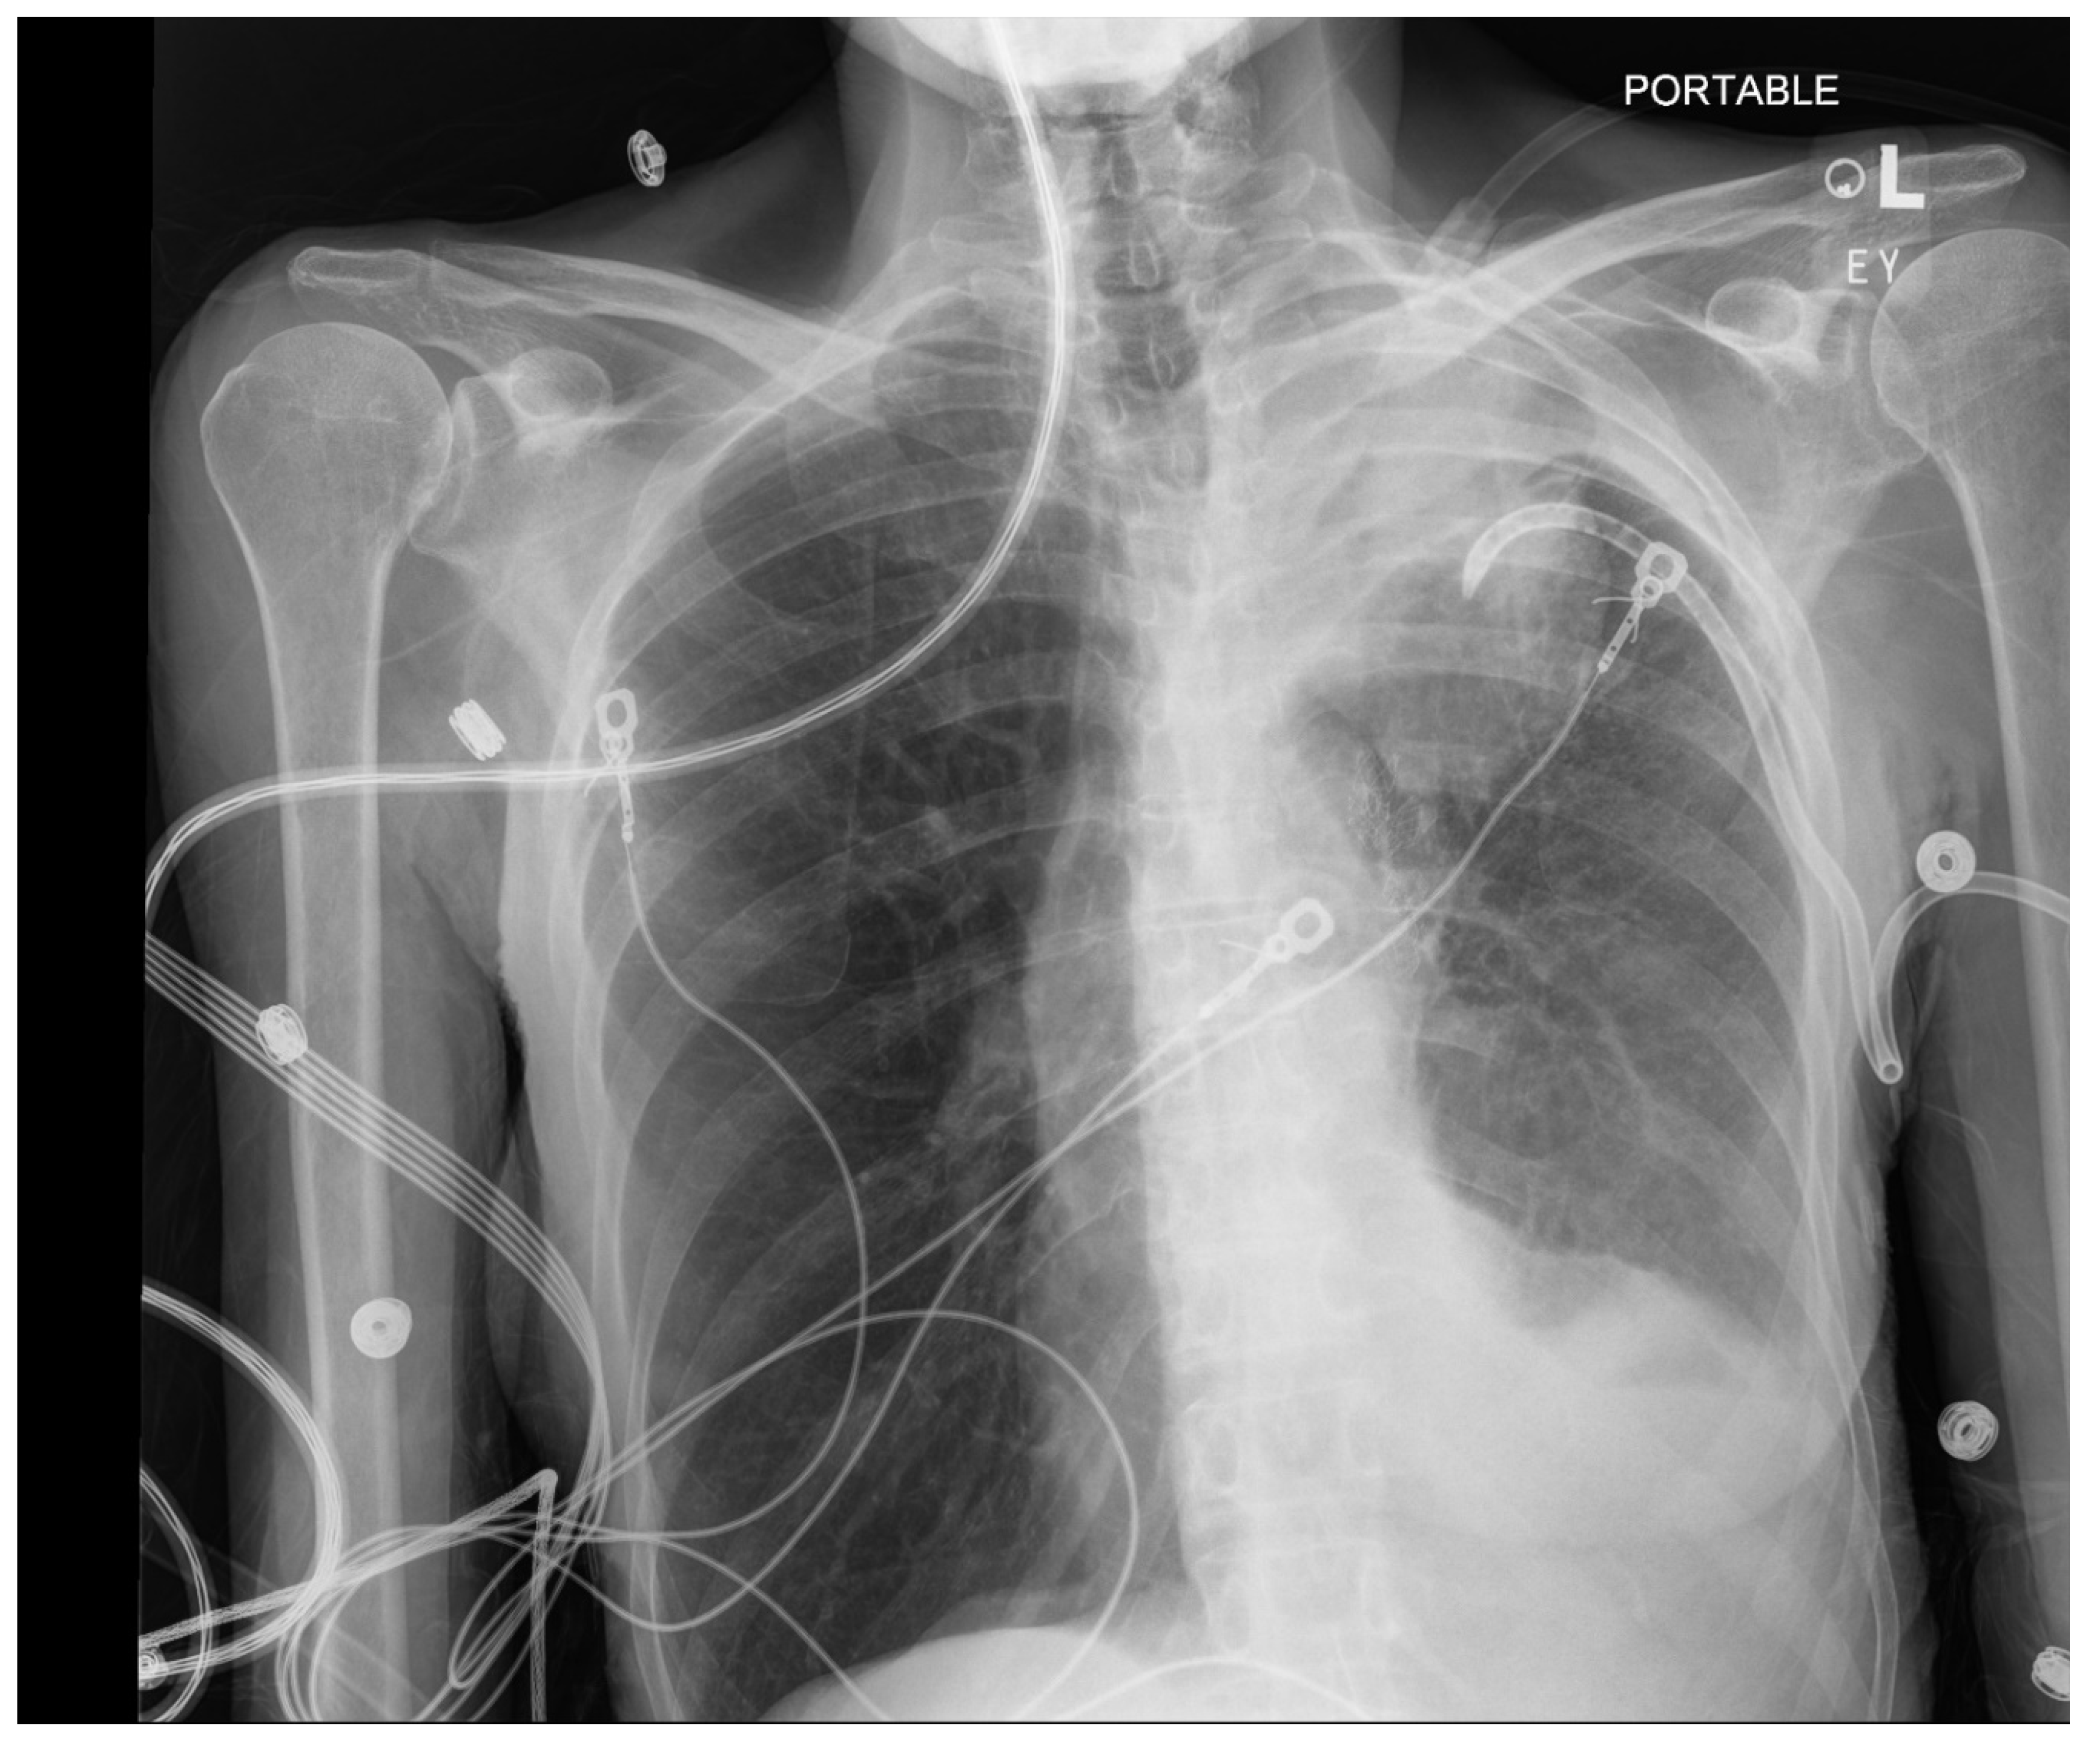

Pneumothorax (Figure 1, Figure 2, Figure 3 and Figure 4) developing after the placement of endobronchial valve (Figure 5) is usually managed by pulmonologists; however, anesthesia providers should be aware. Dijk et al. published their revised expert statement that addresses the issue of pneumothorax extensively [53]. The development of pneumothorax is related to compensatory expansion of the untreated ipsilateral lobe. Such an expansion might result in the rupture of blebs, bullae, and fragile lung tissue [54]. The bronchopleural fistula that develops leads to air leak, which can get worse and become clinically significant very quickly. Pneumothorax can also develop in the vacuum created by therapeutic lung collapse (pneumothorax ex vacuo). The air enters the potential space from the ambient tissues and blood [55]. As there is no bronchoalveolar fistula in this situation, a chest drain is not necessary, and the pneumothorax will spontaneously resolve over time.

Pneumothorax can develop in the immediate postoperative period, in the post anesthesia care unit or within the first 3 days [46,56]. Valipou et al. published their management algorithm for pneumothorax [57]. Nearly 80% of them happen in the first 48 h, 10% in about 3-5 days, and 10% after day 6 [58,59]. Both anesthesia providers and bronchoscopists should be particularly vigilant about the development of tension pneumothorax. Certain post procedural protocols- (cough suppression, strict bed rest, not letting to elevate the arm above shoulders) are employed at Jefferson to minimize the pneumothorax risk. Most pneumothoraces ‘s are treated conservatively with serial imaging. some may require chest tubes and rarely valve removal.

Figure 2. CXR, taken about 16 hours after placement of bronchial valve, Large left pneumothorax with rightward mediastinal shift. Left basilar atelectasis.

Figure 3. CXR Interval placement of a left chest tube. Likely residual loculated pneumothorax at the left lung base. Left upper lobe opacification.